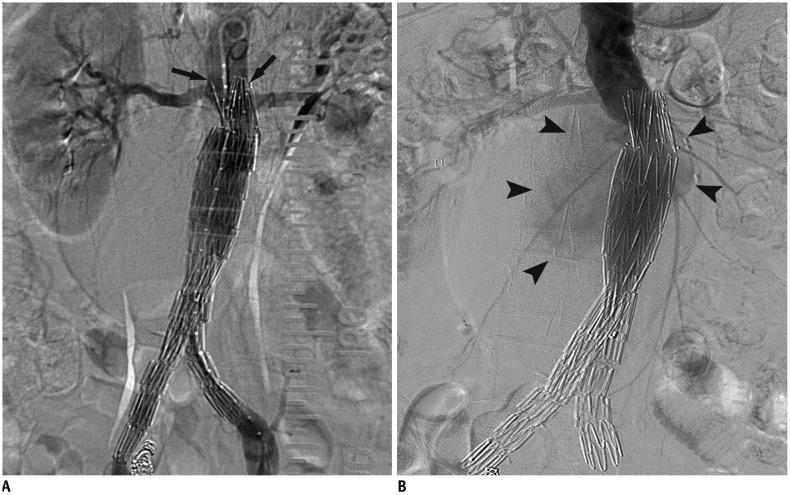

Abdominal aortic aneurysm (AAA) can be defined as an abnormal, progressive dilatation of the abdominal aorta, carrying a substantial risk for fatal aneurysmal rupture. Endovascular aneurysmal repair (EVAR) for AAA is a minimally invasive endovascular procedure that involves the placement of a bifurcated or tubular stent-graft over the AAA to exclude the aneurysm from arterial circulation. In contrast to open surgical repair, EVAR only requires a stab incision, shorter procedure time, and early recovery. Although EVAR seems to be an attractive solution with many advantages for AAA repair, there are detailed requirements and many important aspects should be understood before the procedure. In this comprehensive review, fundamental information regarding AAA and EVAR is presented.

腹主动脉瘤(AAA)可定义为一种腹部主动脉的异常、进行性扩张,具有致命性的动脉瘤破裂的巨大风险。AAA 的血管内修复术(EVAR)是一种微创的血管内手术,涉及在 AAA 上方放置分叉或管状支架移植物,将动脉瘤从动脉循环中排除。与开放手术修复相比,EVAR 仅需要一个刺切口、更短的手术时间和更早的恢复。尽管 EVAR 对于 AAA 修复似乎是一种具有许多优势的有吸引力的解决方案,但在进行该手术之前,需要了解详细的要求和许多重要方面。在本全面综述中,介绍了关于 AAA 和 EVAR 的基本信息。